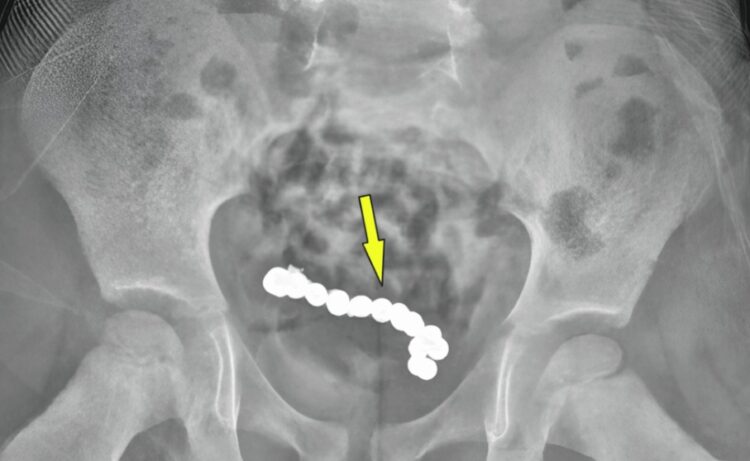

소하르병원 의료진은 남아에게 다시 복부 엑스레이 촬영을 했고, 그 결과 둥근 이물질들이 사슬처럼 연결돼있는 것이 보였다.

이를 제거하기 위한 수술에서 의료진은 총 22개의 자석을 발견했다. 자석들은 서로 붙어 고리 모양을 이루고 있었다. 자석 때문에 장 일부가 괴사해 천공(구멍)이 발생한 상태여서 손상된 장 부위 약 15cm를 절제하고 다시 이어붙이는 문합 수술을 진행했다.